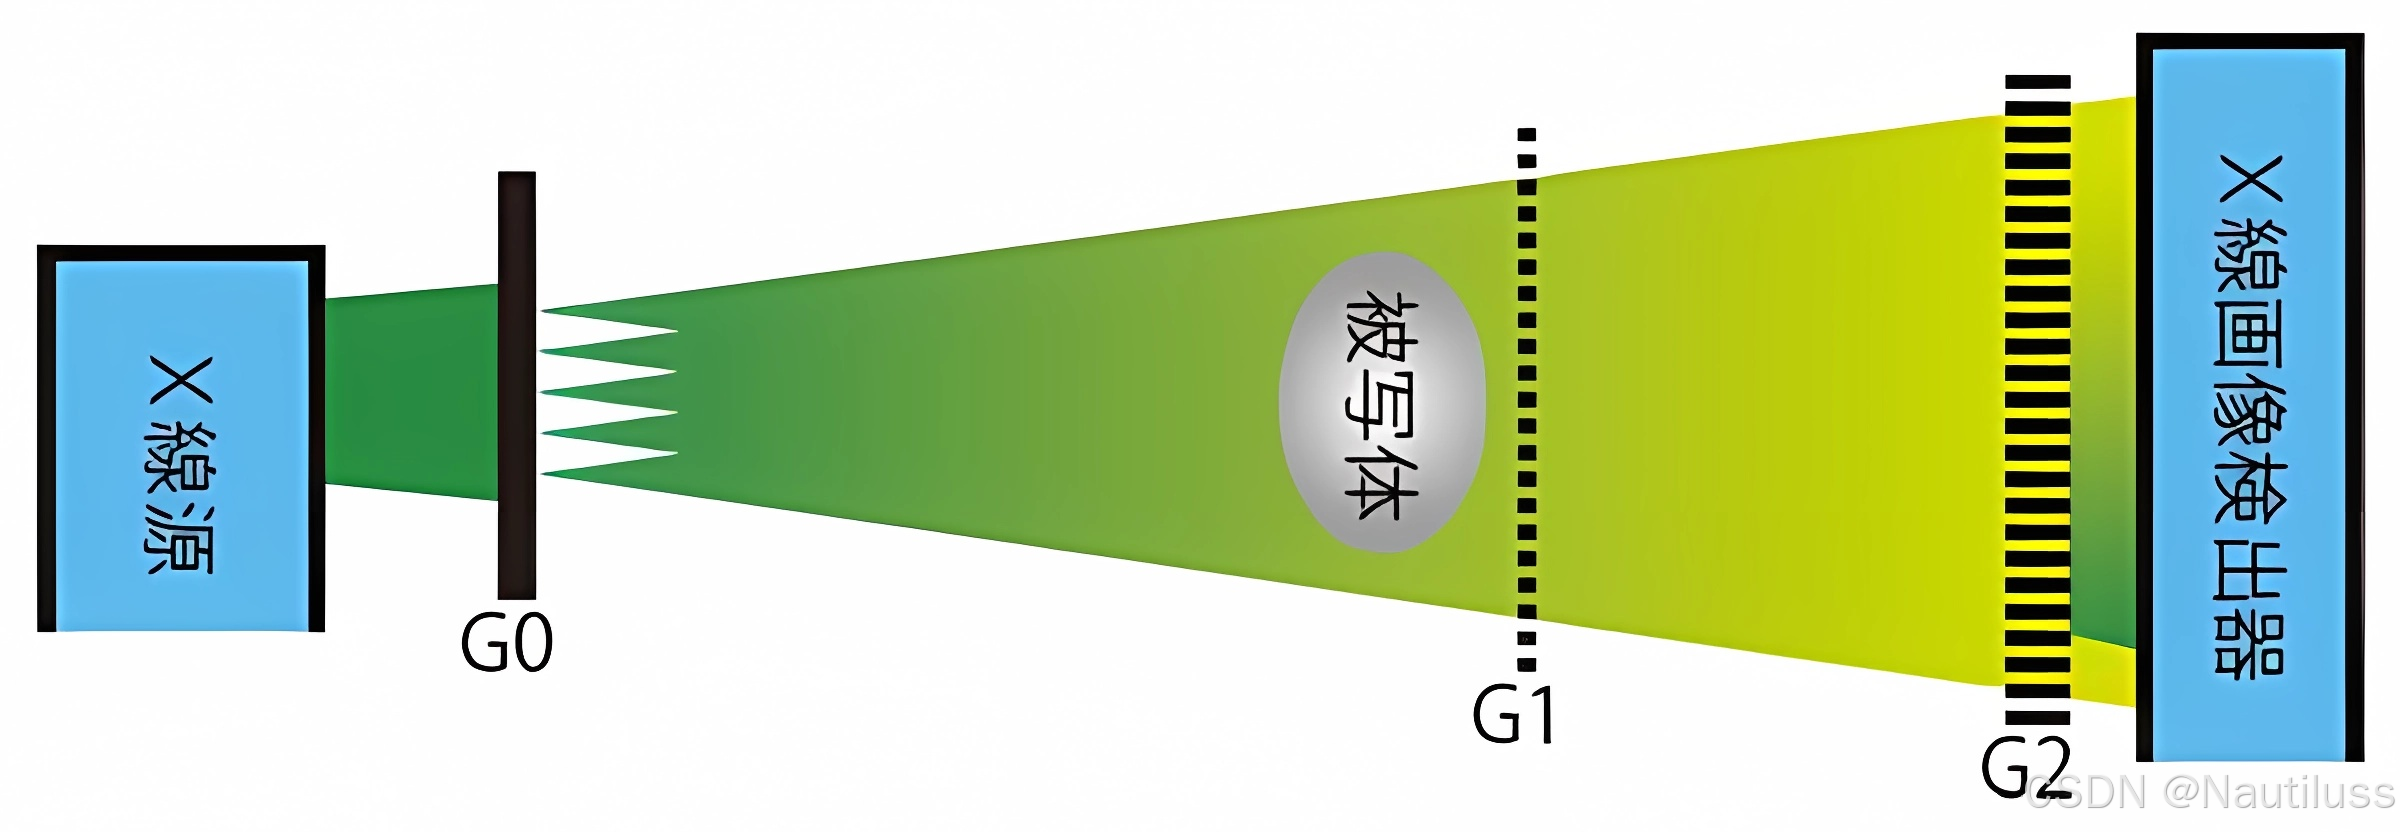

然而,该方法还需要高度相干和高亮度的X射线源,限制了其在实验室源和商业用途中的应用。2006 年,Pfeiffer 等人。在该方法中引入了另一个光栅,因为该光栅紧邻 X 射线源放置。这个光栅创建了一系列单独相干但相互不相干的光源。由于 Lau 效应 ,这些光源的 Talbot 效应在 G2平面上相互重叠,使得该方法适用于非相干和低亮度光源。新引入的X射线光栅干涉仪也被称为“Talbot-Lau干涉仪”。使用 Talbot-Lau 干涉仪时,实验装置中的仪器校准相对简单,可实现大视场。该方法正在成为生物样品最流行的 X 射线相衬图像之一。

医院使用的X射线没有均匀的波,因此不能直接使用塔尔博特效应。通过在 X 射线源附近放置一个额外的网格解决了这个问题。新添加的光栅旨在仅将对齐的 X 射线传递到下游塔尔博特干涉仪。通过这一创新,它将Talbot干涉仪的成像原理应用到已在医院使用的X射线源上,并显着缩短了成像时间。

医院使用的X射线没有均匀的波,因此不能直接使用塔尔博特效应。通过在 X 射线源附近放置一个额外的网格解决了这个问题。新添加的光栅旨在仅将对齐的 X 射线传递到下游塔尔博特干涉仪。通过这一创新,它将Talbot干涉仪的成像原理应用到已在医院使用的X射线源上,并显着缩短了成像时间。